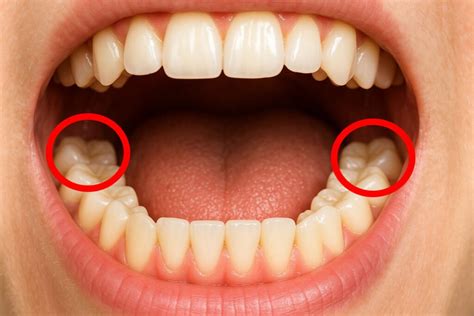

Te estarás preguntando cómo puedes saber si te está saliendo una muela del juicio. Cuando alguna de las muelas del juicio empieza a erupcionar y no encuentra espacio suficiente en la cavidad bucal, es probable que notes algunos síntomas como:

- Enrojecimiento o inflamación de las encías

- Sangrado

- Sensibilidad o dolor en la muela del juicio o en toda la mandíbula

- Jaqueca